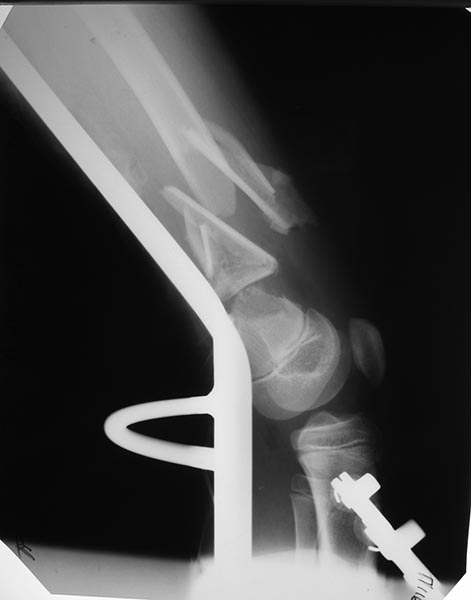

У неё переломы обеих седалищных костей без смещения значительного.

Переломы оскольчатые обеих бёдер в н/3, открытые. Раны ушиты в отличном

состоянии.

На одном бедре межмыщелковый перелом и там мыщелки немного разъехались.

Голень там тоже сломана в н/3 обе кости. Снимок голени в боковой

проекции сделан не был.